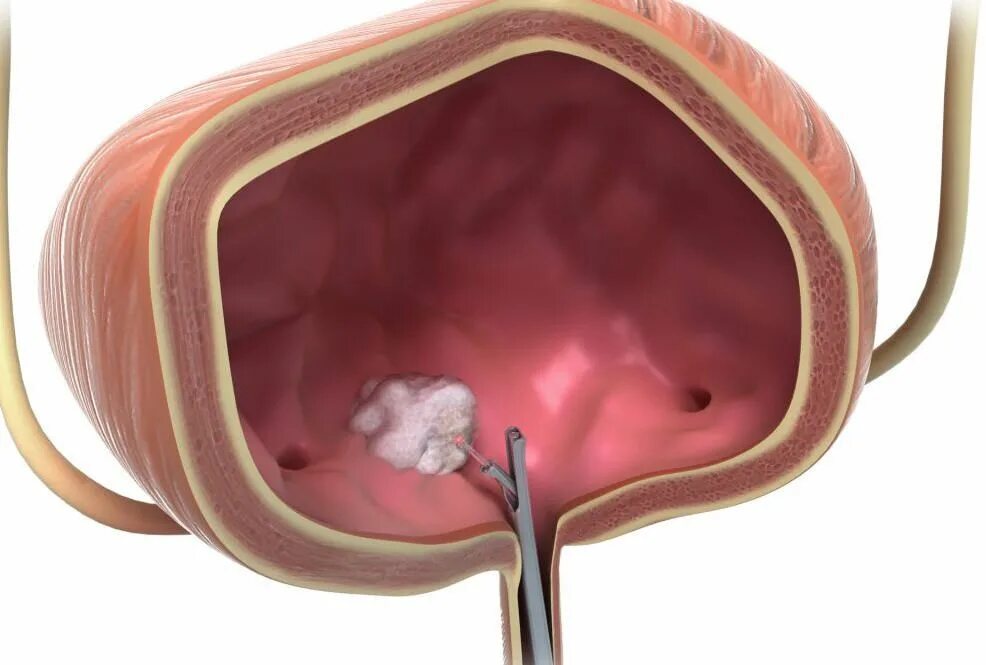

Ощущение в мочеиспускательном канале